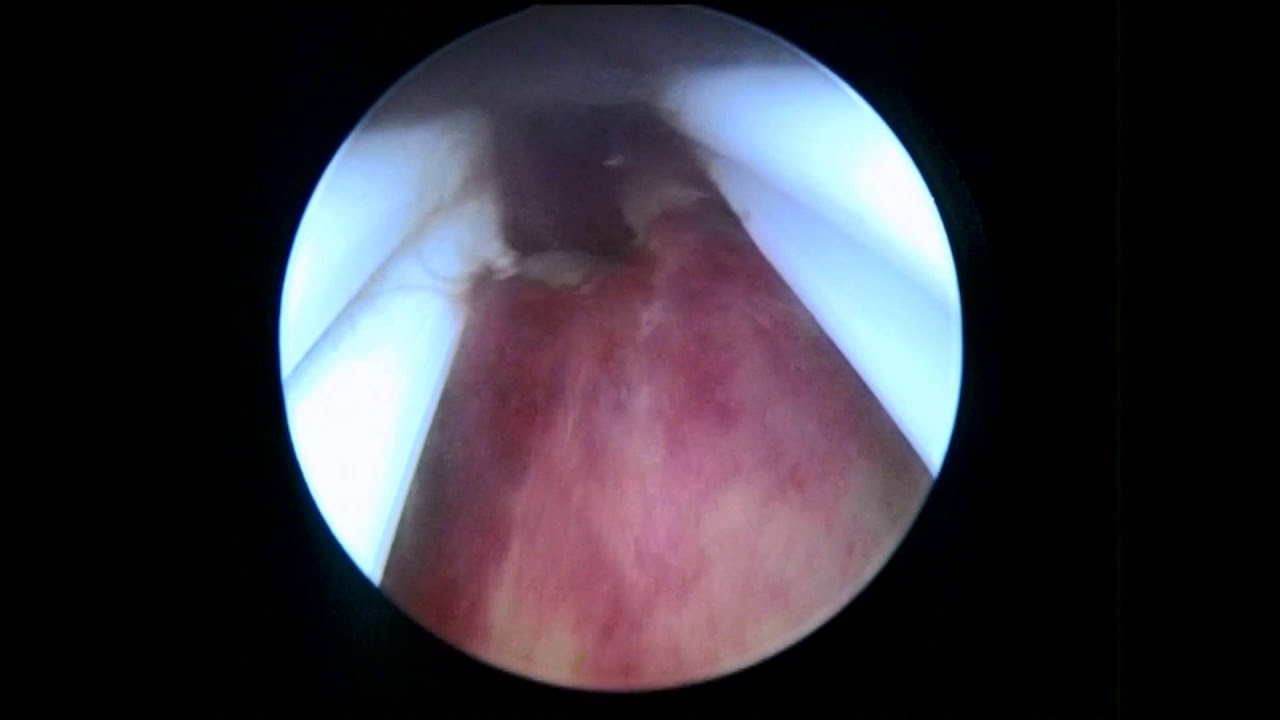

HISTEROSCOPIA diagnóstica || PODEMOS tener un BEBÉ || Pulpito's Family #histeroscopia

Source: Youtube.com